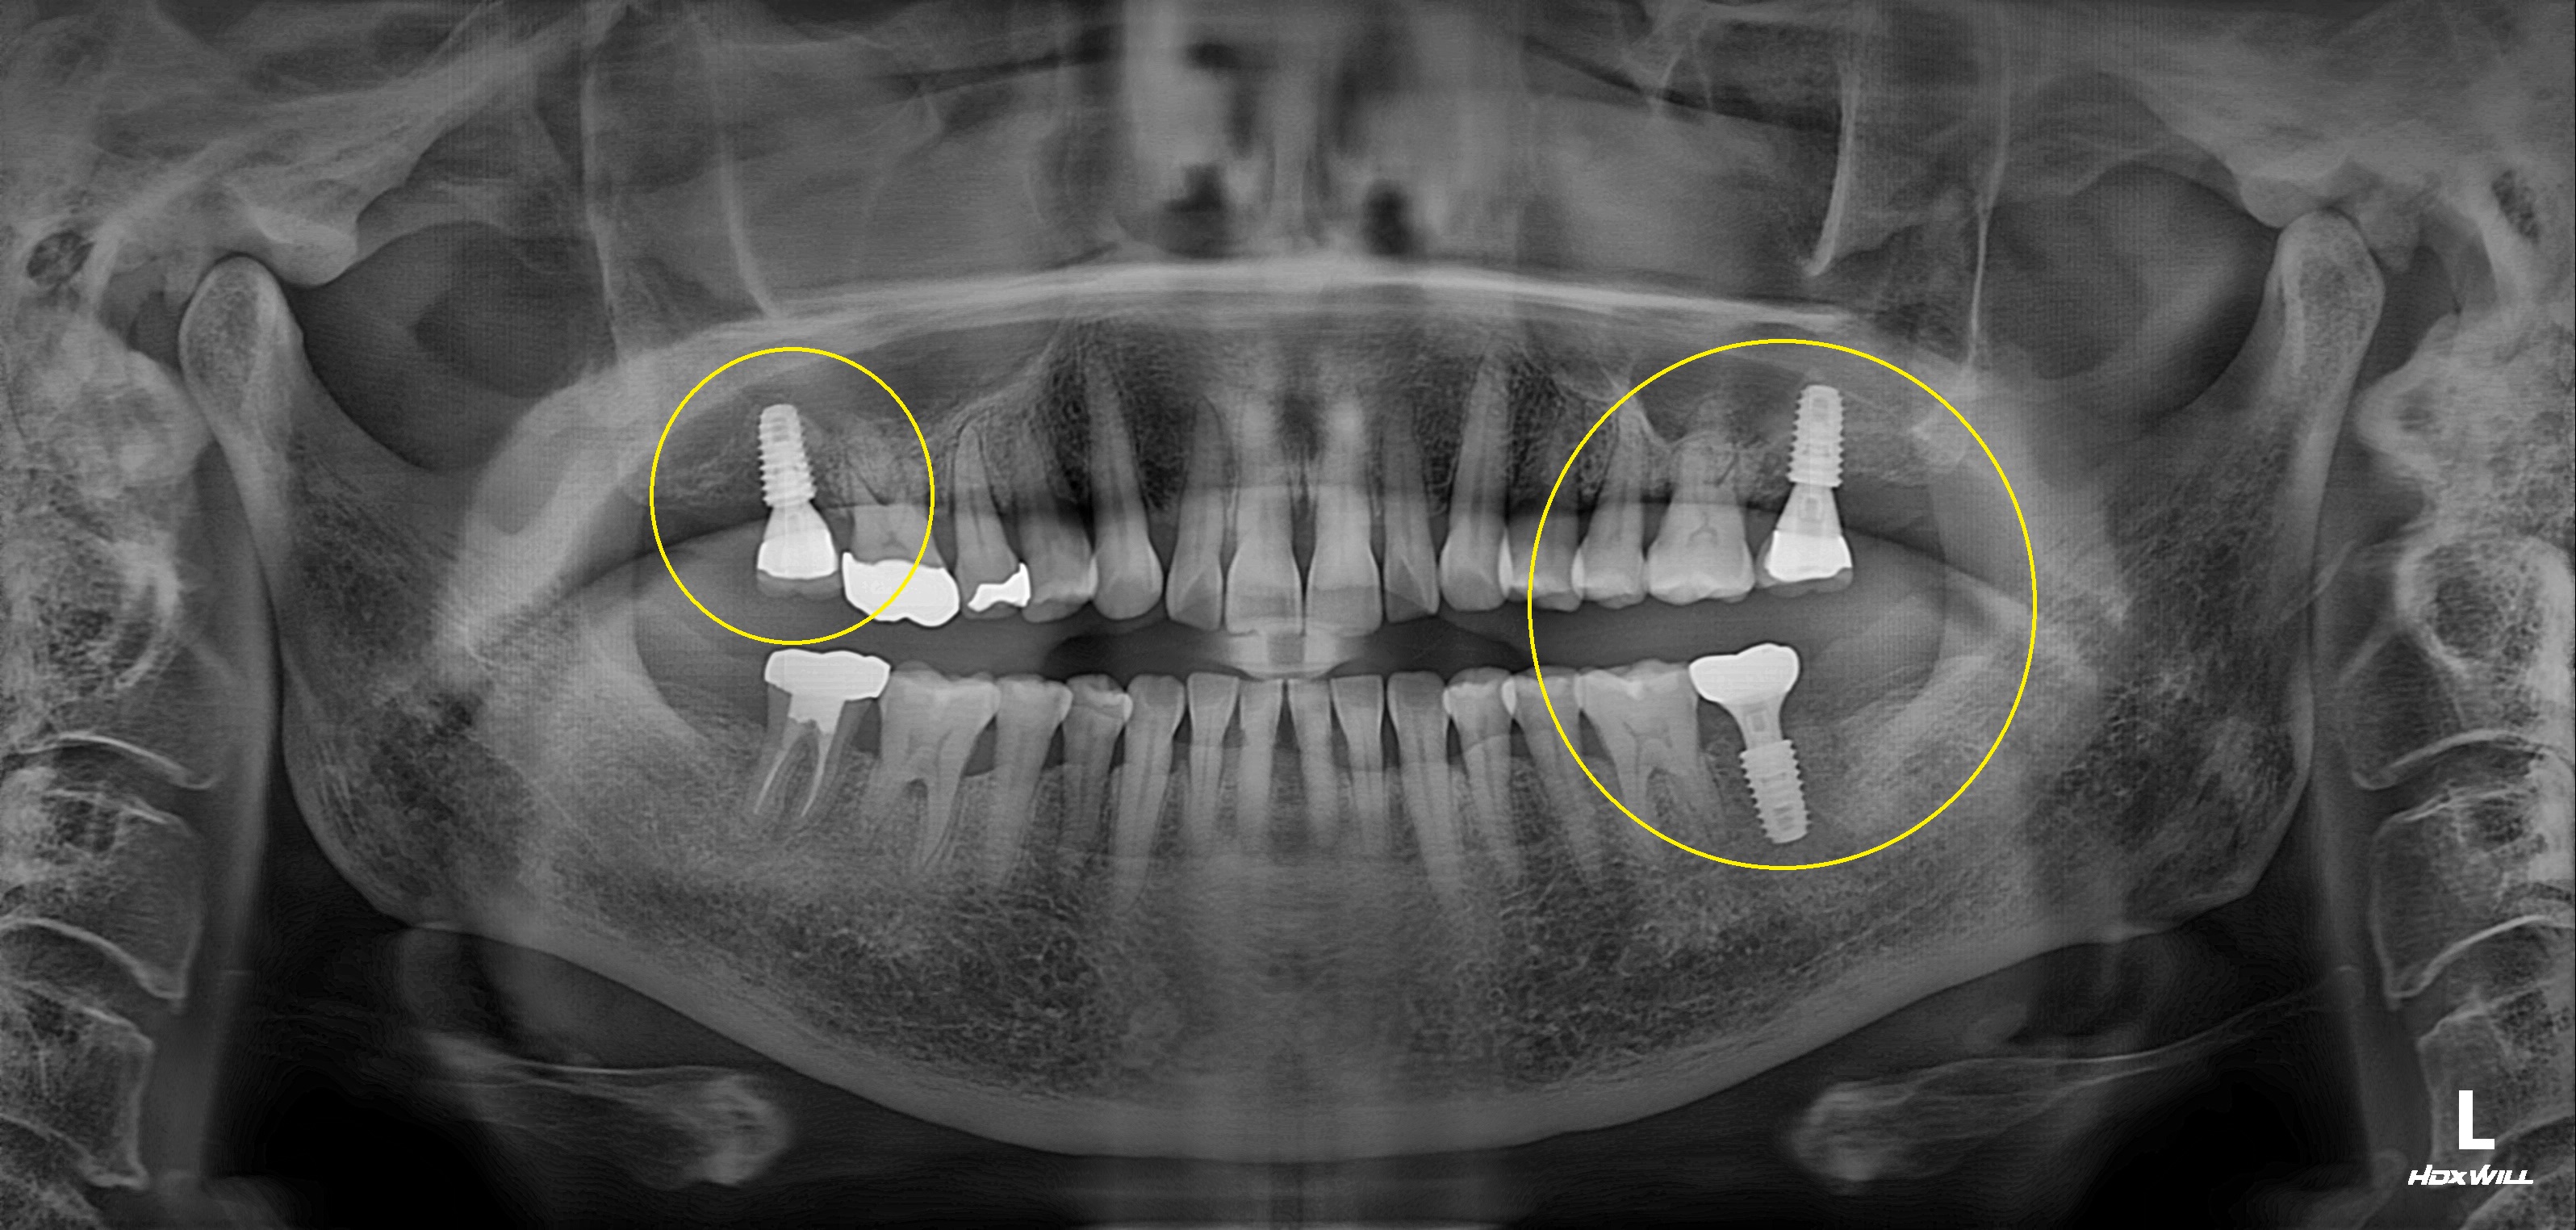

수술 전

수술 후

완전매복치사랑니 발치 + 구치부 임플란트 사례

전후사진